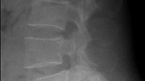

-허리에 무리한 스트레스를 주는 것이 원인평소 운동을 좋아하는 30대 중반의 K씨는 얼마전부터 계단을 오르고 내리거나 무거운 물건을 들 때 마다 허리에 극심한 통증을 느끼곤 하였다. K씨는 본인의 증상이 아무래도 허리디스크인지 의심스러워 찾아간 병원에서 척